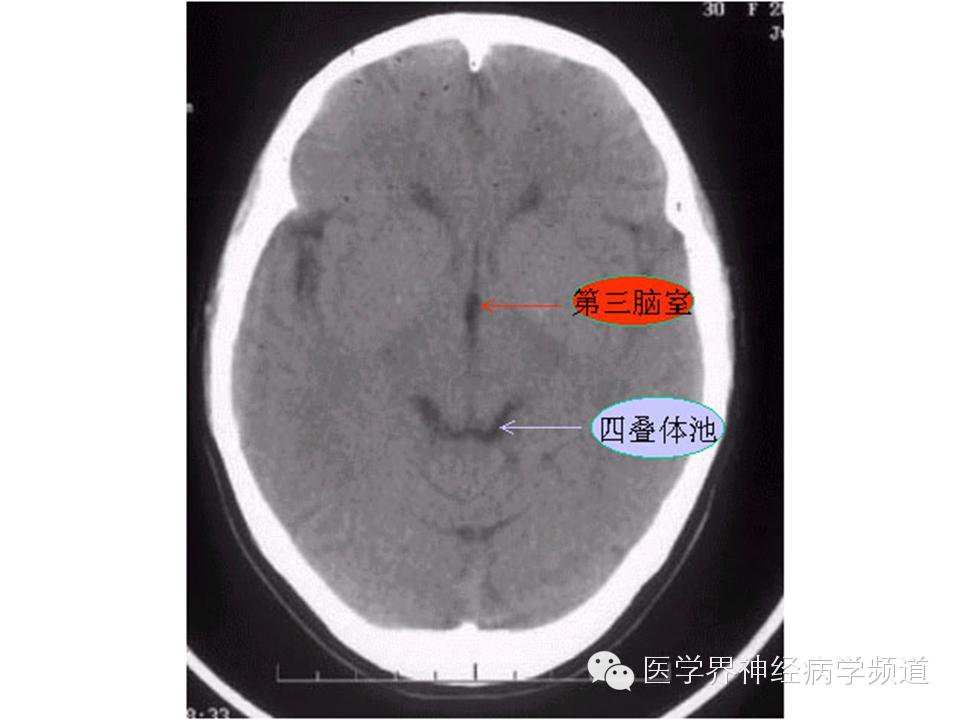

神经影像CT读片step by step